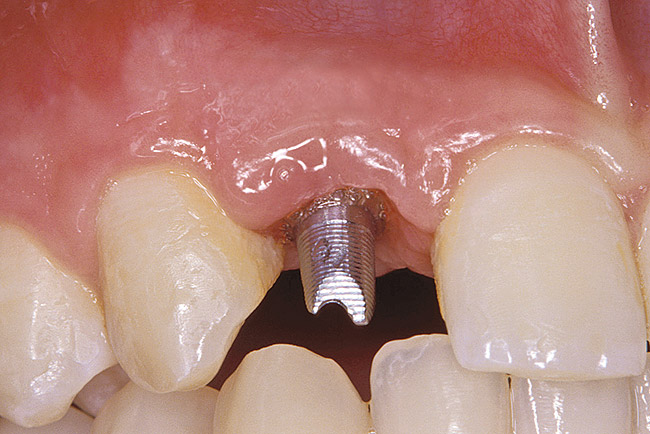

Before the day of surgery, the patient was seen by the orthodontist for the removal of the orthodontic brackets. The patient still was not pleased with the position of the two centrals, and it was determined that this would be addressed after implant placement (Figure 26). The anatomical variations of the crestal tissue and lack of interdental papilla can be appreciated in the close-up views of the right and left sites (Figure 27 and Figure 28). There were no surprises on the day of surgery as all of the decisions were made during the planning phase, before the scalpel ever touched the patient. The occlusal view of the CT 3D model revealed the wider alveolar ridge on the right side and thinner crest on the left side (Figure 29). This was confirmed when the full-thickness mucoperiosteal flaps were elevated, and the underlying bone revealed (Figure 30). The tooth-borne templates were designed to facilitate the drills and drilling sequence specific to the diameters of the predetermined implants (Figure 31). Each template contained an embedded 5-mm long stainless steel tube, which was approximately 0.2-mm wider than each drill (just wide enough to allow for the drills to rotate freely). Once positioned over the natural teeth, the template was secure and offered precision accuracy in transferring the implant locations from the original software-designed plan, allowing the potential for internal and external irrigation (Figure 32).

Figure 33  VIRTUAL PLANNING AND SURGERY After the osteotomies were completed, the implants were placed.

Figure 33

Figure 34  VIRTUAL PLANNING AND SURGERY After the osteotomies were completed, the implants were placed.

Figure 34